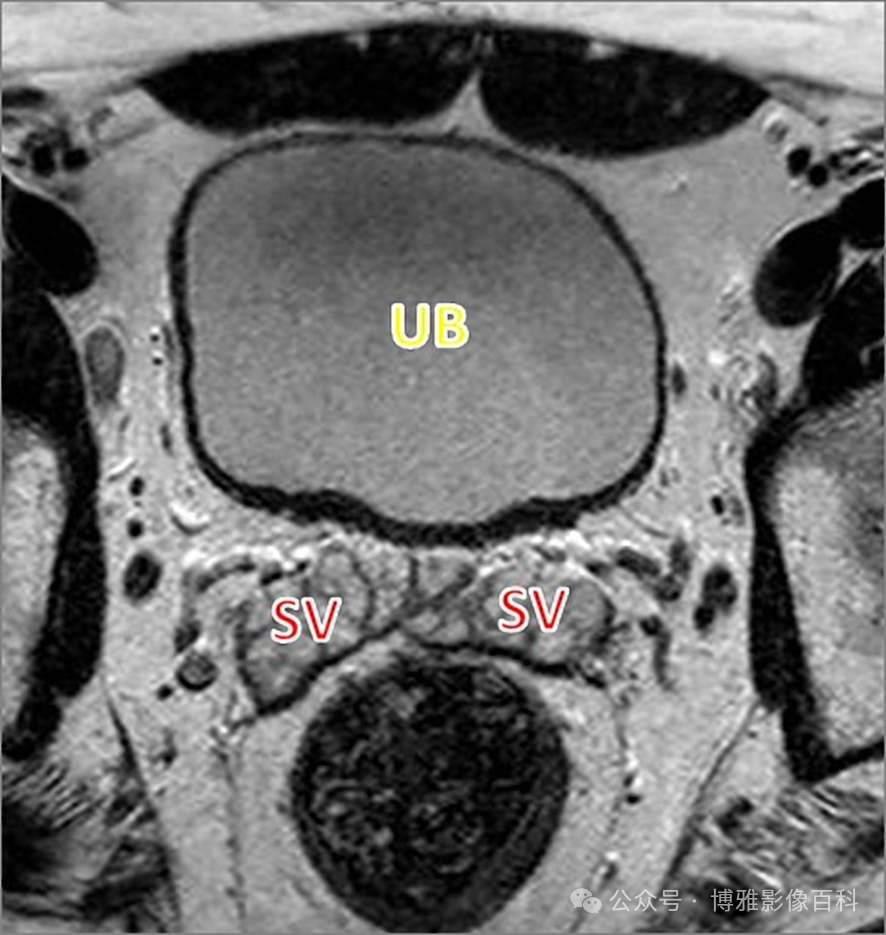

前列腺良性增生患者的轴向T2 图像,其他方面正常。外周带是一薄层均匀的高信号,边界清晰连续性的低信号包膜。移行带通常表现为不均匀中等信号,病灶被边界清楚的BPH良性前列腺增生结节所取代。精囊具有均匀T2高信号。未见淋巴结肿大。